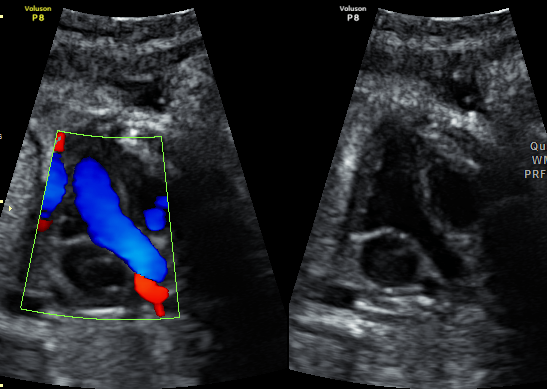

产科_胎心_左室流出道切面